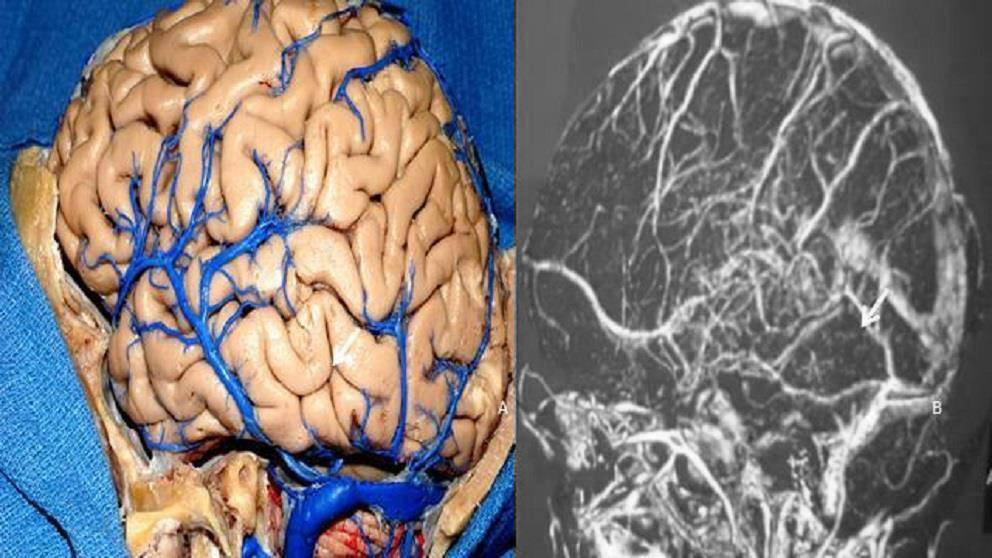

Se disecaron ocho cabezas de cadáveres utilizando un microscopio quirúrgico con un aumento de 3X a 40X. En los cerebros y en todas las cabezas se inyectó silicona de color para resaltar la diferencia entre las arterias y las venas. Los cadáveres se colocaron en un fijador de cráneo tipo Mayfield, con la cabeza extendida y girada, simulando el posicionamiento quirúrgico de los abordajes cráneo orbito-cigomático, petrosectomía anterior, posterior y retrosigmoideo.

Figura 13: El estudio de la posición del drenaje de la vena anastomótica inferior (Labbé) se realiza para evaluar cuando se pretende realizar el abordaje petroso posterior. La vena de Labbé comúnmente drena en la unión de los senos transverso y sigmoideo (flecha). Pieza anatómica (A). Resonancia venosa (B).